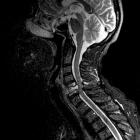

Магнитно-резонансная томография сосудов (МР-ангиография) дает возможность проводить исследования сосудов без введения контрастных веществ в нескольких взаимно перпендикулярных плоскостях. Развитию техники МРА способствовали наблюдения, показывающие, что движущийся поток при некоторых условиях может вызывать изменения МР-сигнала. В результате были разработаны программы, предназначенные для изучения сосудистых структур, нацеленные на усиление сигнала потока крови с одновременным погашением сигнала от неподвижных тканей. Для получения МР-изображения более высокого качества рекомендуется исследование на фоне введения контрастных средств (парамагнетиков).

Кроме того, томографические методы диагностики дают возможность судить об изменениях в ишемизированном органе: например, диагностировать изменения, происходящие в головном мозге у больных с поражением брахиоцефальных артерий (ишемические очаги, постинсультные кисты и т. д.) (рис. 3), а также изучать изменения перфузии вещества головного мозга. При обследовании пациентов с подозрением на вазоренальную гипертонию томографические методы позволяют получать изображение не только почечных артерий, но и надпочечников, выявлять происходящие в них изменения (гиперплазию, опухоли) и таким образом исключить (подтвердить) гипертензию надпочечникового генеза, определить состояние почечной паренхимы.